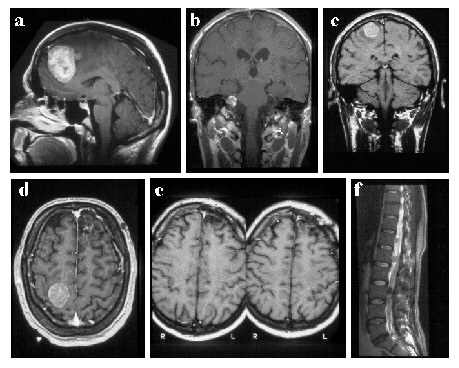

Beispiel einer interdisziplinären Therapiestrategie bei einem Patienten mit metastasierendem malignem Melanom. Ein 18jähriger junger Mann erkrankt an einem malignem Melanom am Oberschenkel. Es erfolgt die operative Exstirpation. 13 Jahre später entsteht eine frontale Hirnmetastase (a). Der Patient wird durch einen Krampfanfall auffällig. Operative Entfernung der Hirnmetastase. Postoperativ wird keine Ganzhirnbestrahlung angeschlossen. Sieben Monate später tritt eine periphere Fazialisparese rechts auf. Im MRT wird eine Metastase im Kleinhirnbrückenwinkel festgestellt (b). Es erfolgt eine radiochirurgische Therapie. Auf eine operative Therapie wird verzichtet. Ein halbes Jahr später tritt eine linksseitige Hemiparese auf. In der MRT zeigt sich rechts zentral eine erneute Metastase (c, d). Der Tumor im Kleinhirnbrückenwinkel hat nicht an Größe zugenommen. Auch links frontal im alten Operationsbereich wird ein unauffälliger Befund erhoben. Die zentrale Metastase wird operativ exstirpiert (e). Danach erfolgt eine postoperative Ganzhirnbestrahlung. Die neurologische Symptomatik bildet sich zurück. Ein halbes Jahr später stellt sich der Patient erneut mit starken Schmerzen im Lendenwirbelsäulenbereich vor. In der MRT werden nun multiple Metastasen intradural in der BWS, LWS und dem Os sacrum nachgewiesen (f). Es erfolgt eine Bestrahlung der spinalen Achse. Insgesamt überlebte der Patient zwei Jahre nach Diagnose der ersten Hirnmetastase.